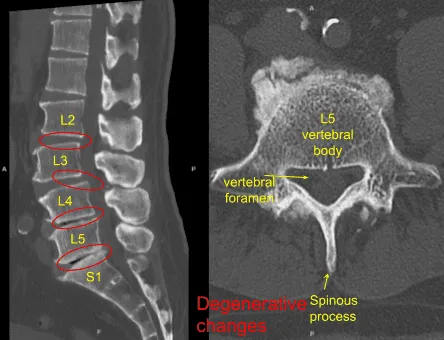

Me hicieron una resonancia magnética que mostró cambios degenerativos de L2 a S1 con retrolistesis en L2-L3, anterolistesis de grado 1 en L3-L4, fenómenos de vacío en L4-5 y L5-S1 con pérdida de espacio discal en L4-L5 y L5-S1.